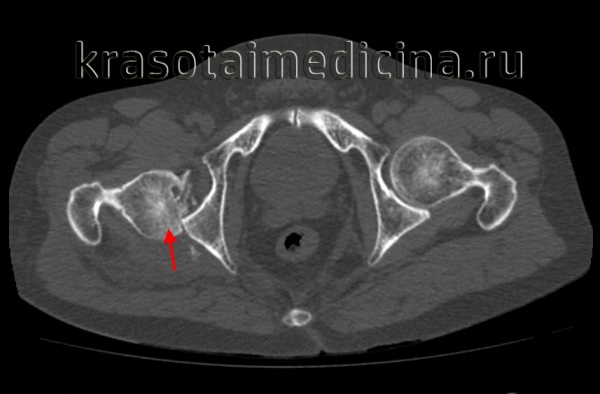

КТ таза. 3D-реконструкция. Красная стрелка – вывихнутая головка бедренной кости, синяя стрелка – «пустая» вертлужная впадина.